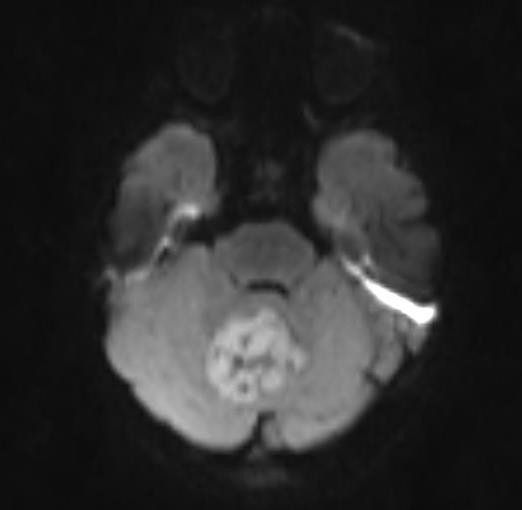

Plano axial ponderada em T2 (TSE) com presença de formação expansiva de contornos ligeiramente lobulados, localizada na metade superior do vermis cerebelar, acompanhada por halo de edema vasogênico, determinando compressão com deslocamento anterior do IV ventrículo, e leve compressão sobre os pedúnculos cerebelares superiores.

Ressonância Magnética:

- T1 hipointenso a massa cinzenta

- T1 C + (Gd) melhora geral de 90%, muitas vezes de forma heterogênea

- T2 / FLAIR em geral são iso a hiperintensos a matéria cinzenta heterogêneo devido à calcificação, necrose e formação de cisto edema circundante é comum

- DWI / ADC sinal DWI alto ("difusão restrita") valores de ADC baixos (cerebelo mais baixo do que o normal, por exemplo, ~ 550 x 10-6 mm2 / s)

A ressonância magnética é capaz de delinear o quarto ventrículo e o espaço subaracnóideo em um grau muito maior do que a TC. Embora os meduloblastomas se projetem para o quarto ventrículo, ao contrário dos ependimomas, eles geralmente não se estendem para as cisternas basais